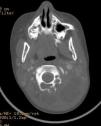

Se realiza una tomografía computarizada cervical (fig. 1), donde se observa una lesión quística de contenido heterogéneo con septos en su interior, con paredes bien definidas y sin vascularización interna ni periférica, que indica el diagnóstico de linfangioma sobreinfectado. Así mismo se evidencia afectación ósea adyacente en los arcos posteriores de C2 y C3. La resonancia magnética (fig. 2) permite la visualización de la extensión de la masa hasta espacio epidural, con desplazamiento de la médula espinal. Para su estudio etiológico, se realiza la punción aspiración de la tumoración, evidenciándose contenido lechoso purulento, presentando un crecimiento positivo cultivo a Staphylococcus aureus compatible con material linfático sobreinfectado. El estudio histopatológico de la muestra evidenció tejido necrótico-hemorrágico sin presencia de atipias. Se realizó un drenaje quirúrgico de la lesión y se inició antibioterapia empírica por vía intravenosa con evolución favorable.